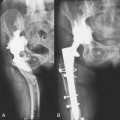

Short external rotators and trochanteric bursa should be repaired with care; the repair is tested with hip flexion before closure of the fascia.The posterior or Moore Southern approach is the most popular technique for total hip arthroplasty. It has some marked advantages over other approaches to the hip. Less extensive tissue dissection is needed with this approach than with others, and this approach does not violate the abductor mechanism. Therefore, patients have a lower incidence of postoperative Trendelenburg gait. The exposure also provides good access to the acetabulum and the femur and can be extended either proximally to address pelvic dissociation with plating of the posterior column, or distally to address femoral fracture. The posterior approach is associated with a lower incidence of heterotopic bone formation. It has a historically higher dislocation rate compared with the anterolateral approach, but this is not the case when an enhanced posterior repair is used.1

After trying for seven years to reduce the problems encountered with hip resurfacing, we advocate the posteroinferior approach. The approach has all the benefits of our standard posterior approach: it preserves all cutaneous nerves by passing between the known angiodermatomes2; preserves the iliotibial band and the trochanteric bursa; and avoids any dissection of the gluteus medius and minimus, which improves abductor function and reduces the risk of heterotopic bone formation.